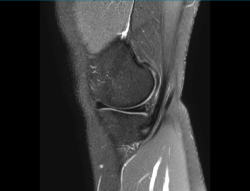

4.3. Osteocondritis

En la osteocondritis se aprecia una lesión subcondral caracterizada por resorción ósea, colapso y la formación de un secuestro.

El estudio por RM es una herramienta valiosa para diagnosticar e identificar las lesiones del cartílago. Conocer el aspecto del cartílago y saber cuánto y cuándo se lesiona, basándose en las clasificaciones actuales, permiten al radiólogo proporcionar la máxima información al clínico(20).

Figura 53. Corte de secuencia sagital (A) y axial (B) T2 Fat-Sat de RM de rodilla: lesiones osteocondrales en el fémur y la rótula.

Numerosos estudios demuestran la utilidad de la RM para definir la estabilidad o inestabilidad de la lesión en la osteocondritis, destacando su carácter no invasivo y la capacidad de valorar la progresión y la respuesta al tratamiento(21)(Figuras 53 y 54).

Figura 54. Corte de secuencia T1 y T2 Fat-Sat coronal de resonancia magnética: gran osteocondritis en el cóndilo femoral interno con edema en la medular adyacente.